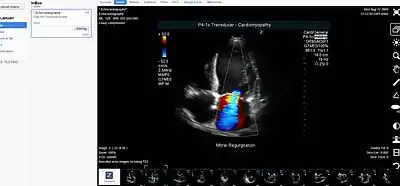

An image displayed on a medical image sharing platform